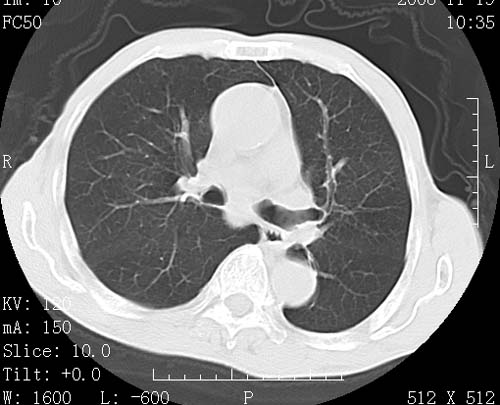

术前查体,双肺部结节是转移?结核?请点评

1)符合食管癌表现。2)两肺及纵隔淋巴结多发性转移瘤。3)左肺上叶舌段及两肺下叶炎症感染。

食管癌伴双肺转移,评述:肺部毛细血管网丰富,全身血液均快速流经肺部,癌细胞容易过滤定植,形成转移瘤,影象特点为以毛细血管末梢为中心的结节灶,边缘光滑锐利,少见有中心空洞着,不同来源的转移瘤可有各自特点,如甲状腺癌为双肺弥漫性微结节,本例有原发灶,双肺影象灶典型,左肺舌段条带状网格样伴胸膜天幕征,可视为癌性淋巴管炎。

符合食管癌表现。两肺及纵隔淋巴结多发性转移瘤。双肺还有支扩表现.

左肺舌段有斑点钙化灶,能否说明是结核而不是转移?如果是转移将放弃手术改成化疗,如果是结核将考虑择期手术